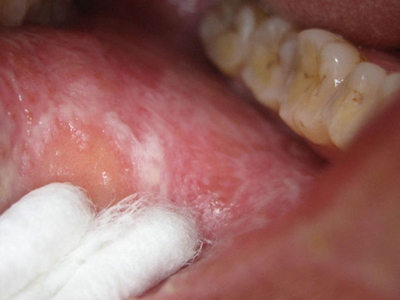

口癣一般指口腔扁平苔藓,是累及口腔,与细胞介导免疫功能紊乱有关的慢性炎症性疾病。好发于中年人,且女性多于男性,通常病程较长。患病后,临床特征为口腔黏膜损害,早期没有自觉症状,也容易被忽视,多在检查时偶然发现,其具体病因不明,通常在治疗时也需给予药物治疗及生活调理。

口癣的临床特征为口腔黏膜损害,主要为珠光白色条纹或网纹,也可为单线条或绕成环形。在舌背多为圆形或椭圆形白色斑块,损害区乳头消失而平伏。软腭或其他部位可发生透明颗粒状水疱。条纹之间的黏膜色泽可以正常或充血;有时在损害范围内某一区域发生糜烂,在唇部或颊黏膜处有时可出现针头大小、微隆的丘疹。